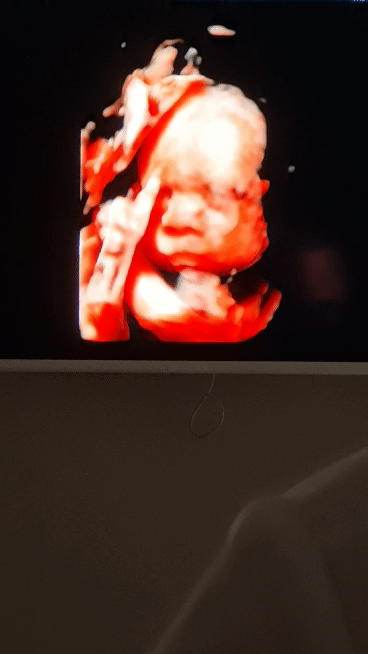

3Д УЗИ в 26 недель, фотопуз)

Вот такая красота получилась😋

Что-то жевала, бормотала, улыбалась и показывала свой маленький язычок)

Это ж у меня две модели будет теперь, откуда брать памяти на телефоне столько 🤣Похожа на сестричку, ну суждено мне красивых баб рожать 😁 Скромность, не, не слышали)